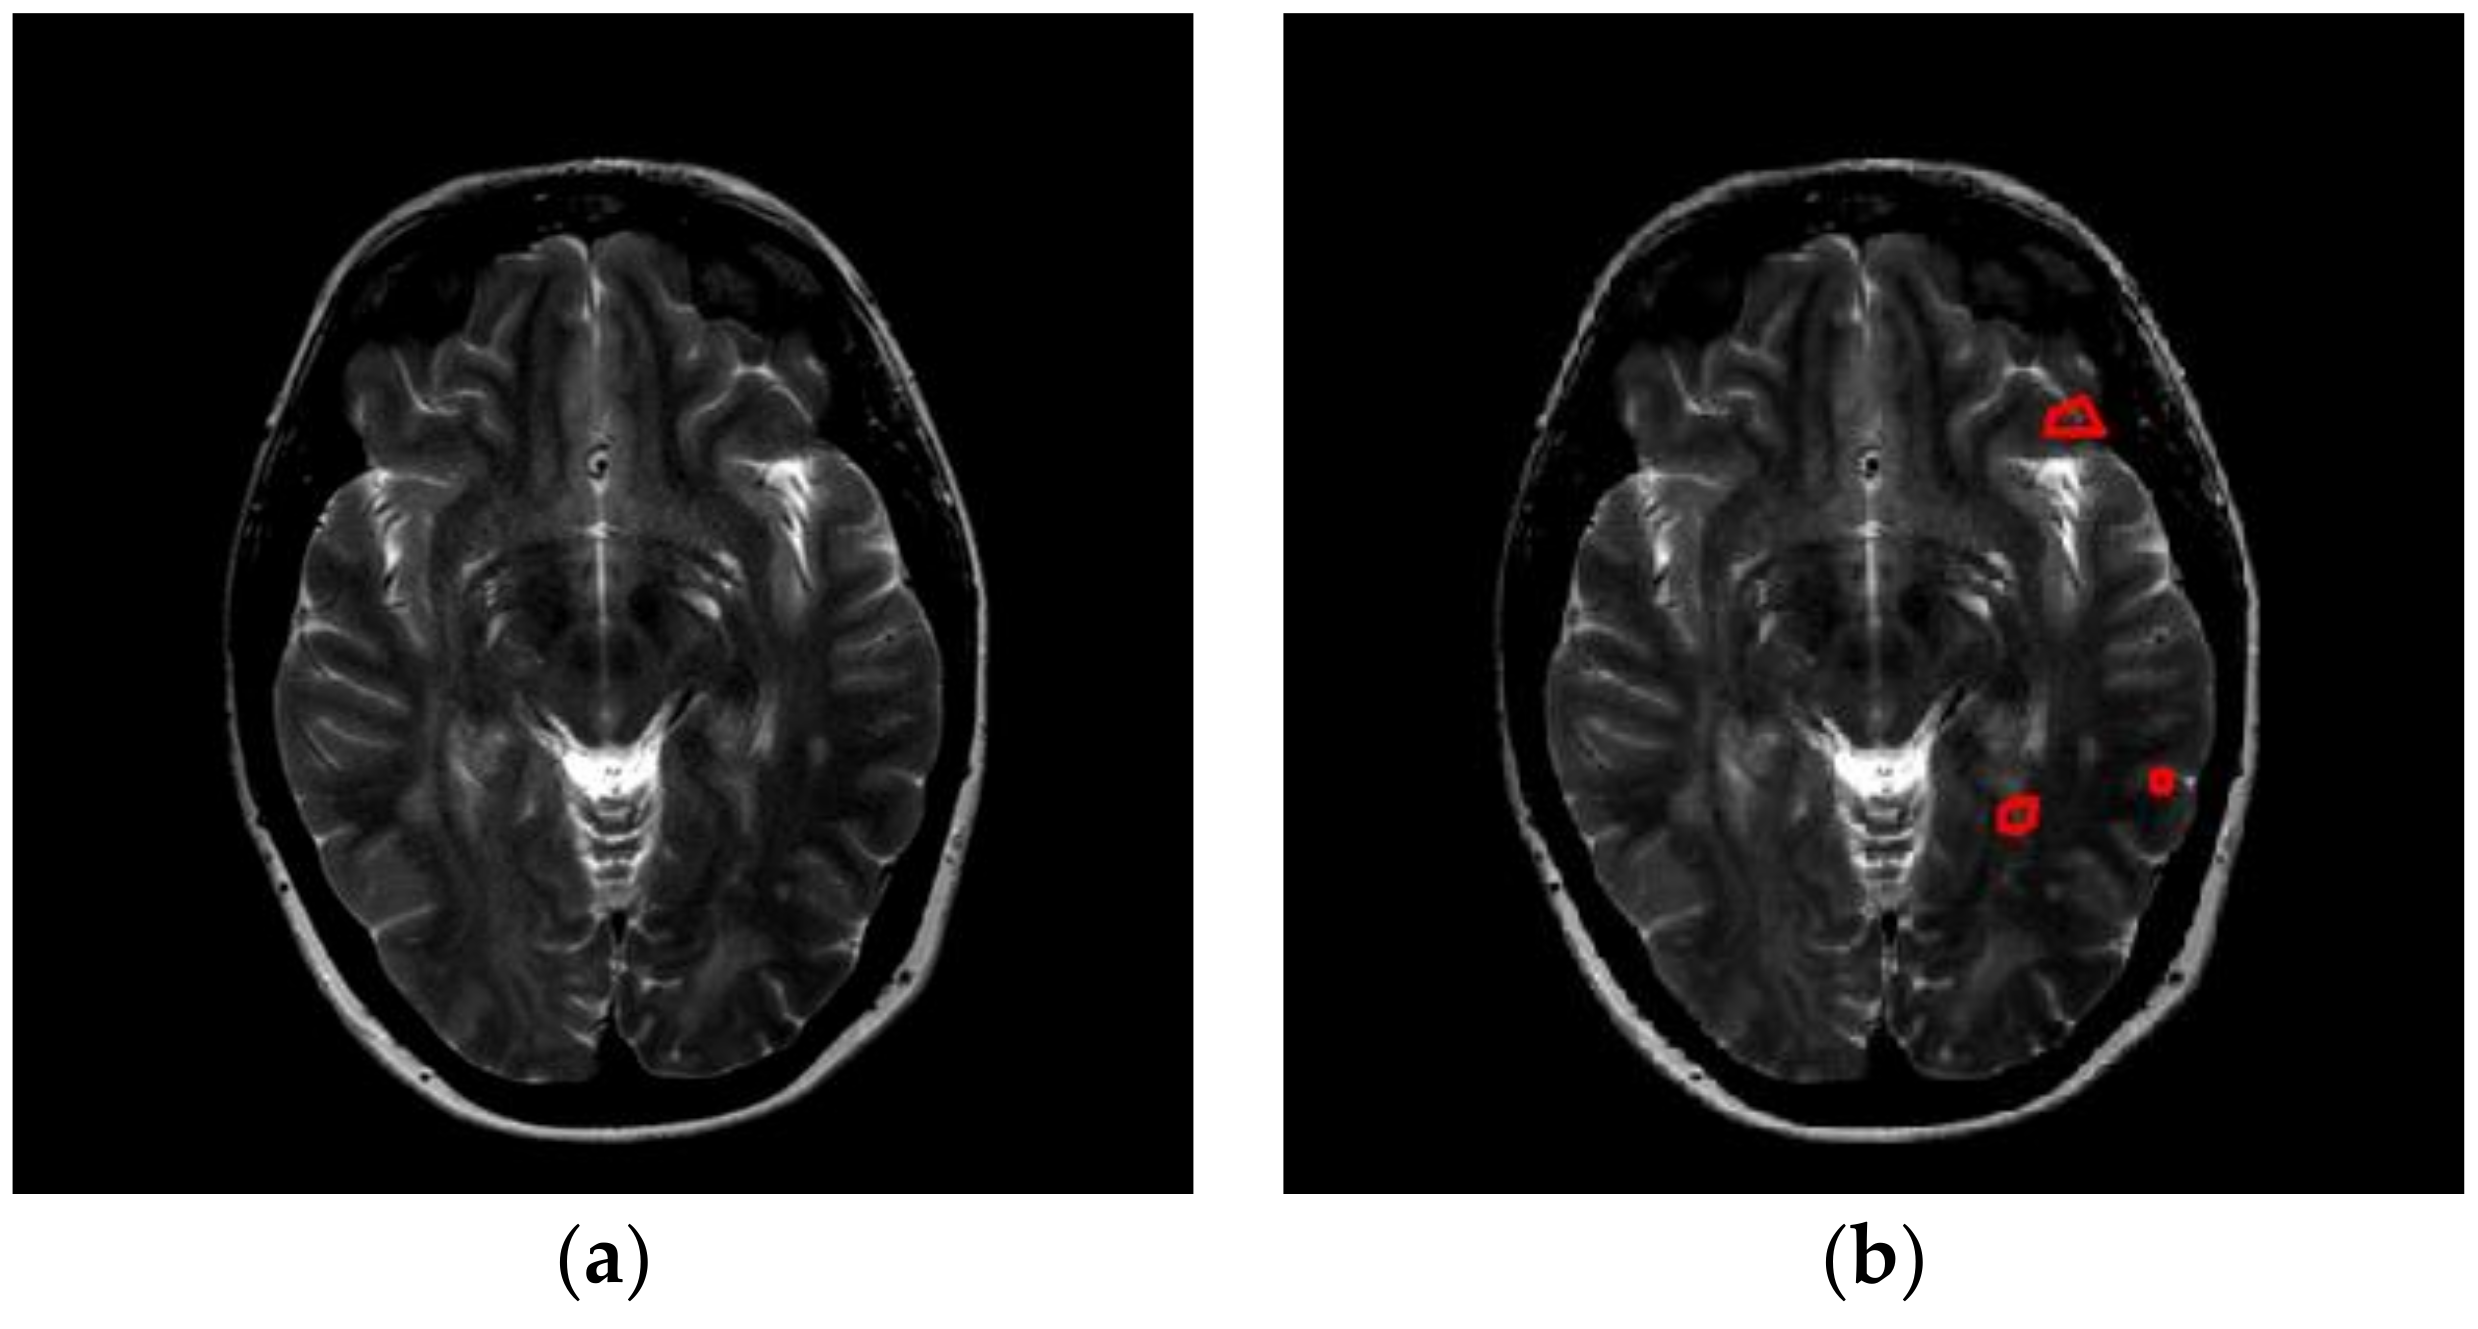

The images used in this study come from two sources. First, we downloaded brain images from the eHealth laboratory [13]. There are 38 patients (aged 34.1 ± 10.5 years, 17 males and 21 females) in the dataset. All brain lesions were identified by experienced MS neurologists, and were confirmed by radiologists. We selected the slices that were associated with plaques, and finally obtained 676 slices altogether. Figure 1 and Figure 2 shows two slices with three and five plaques, respectively. The expanded disability status scale (EDSS) of starting scores are 2.2 ± 0.8. After five years, the EDSS scores of all 38 patients were 2.85 ± 1.5 [14].

Figure 1. A slice with three plaques (areas surrounded by red lines denote the plaque). (a) Original Image; (b) Delineated.